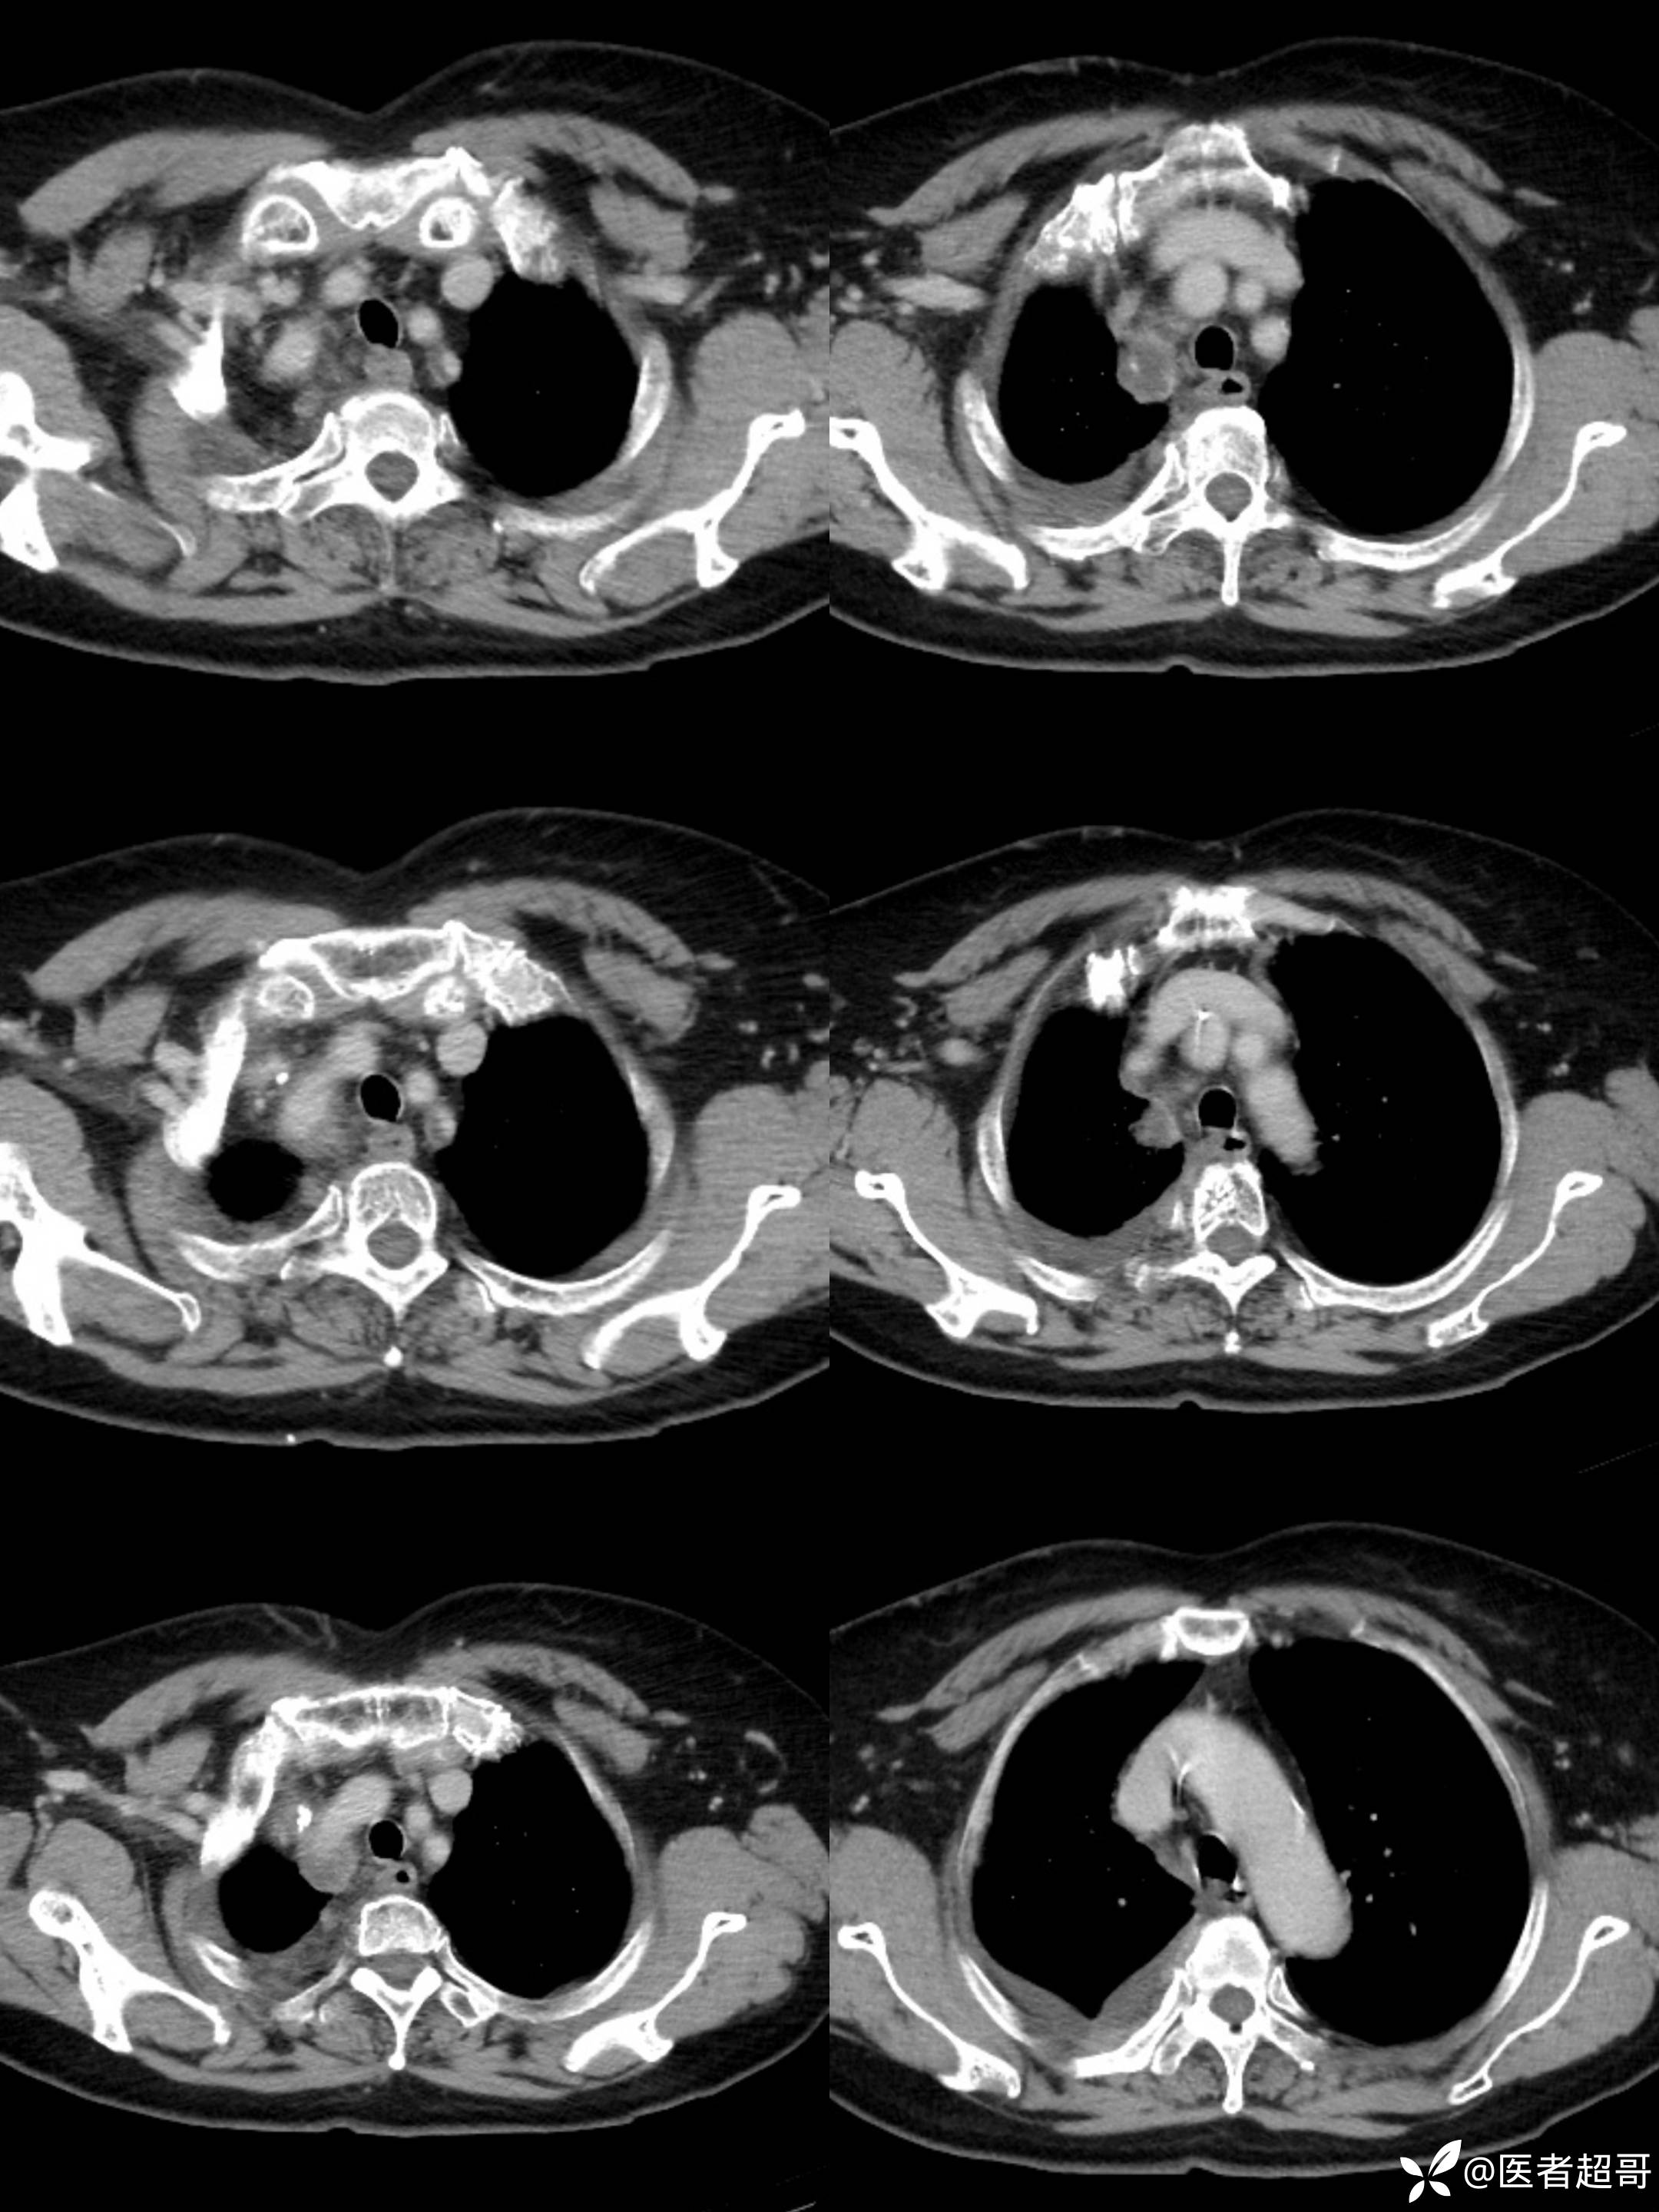

女65岁,患者于一月前无明显诱因突发右胸背部疼痛不适,呈阵发性疼痛

结核特异性细胞(TB-I) 阴性;超敏反应C蛋白(hsCR) 18mg/L ↑,其余血常规正常;

纵隔良性畸胎瘤 (1)